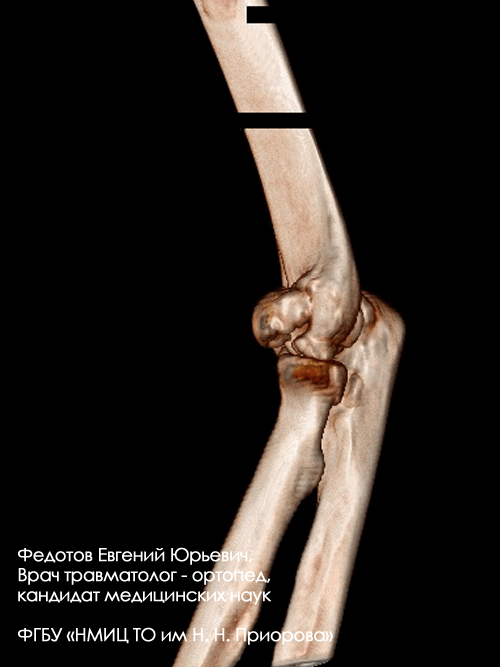

Закрытый внутрисуставной перелом головочки, блока мыщелка и наружного надмыщелка плечевой кости со смещением.

Операция: открытая репозиция отломков дистального мыщелка плечевой кости, наружного надмыщелка, остеосинтез пластиной и винтами.